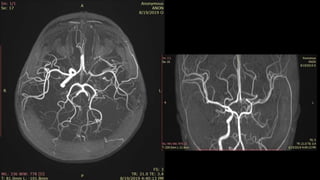

2D TOF MIP MRA 3D TOF VRT MRA

BILATERAL CAROTID MRA TOF MIP

LEFT ICA STENOSIS

• #63 Here is TOF MIP and VRT MRA showing excellent angiogram due to background suppression and better flow related signal leading to better distal small vessel visibilty

• #64 here is an example of AP VIEW of normal MR angiogram of cervicocranial arterial system

• #65 In this MR angiography of bilateral carotid system there is e/o short segment narrowing of Left ICA s/o left ICA stenosis